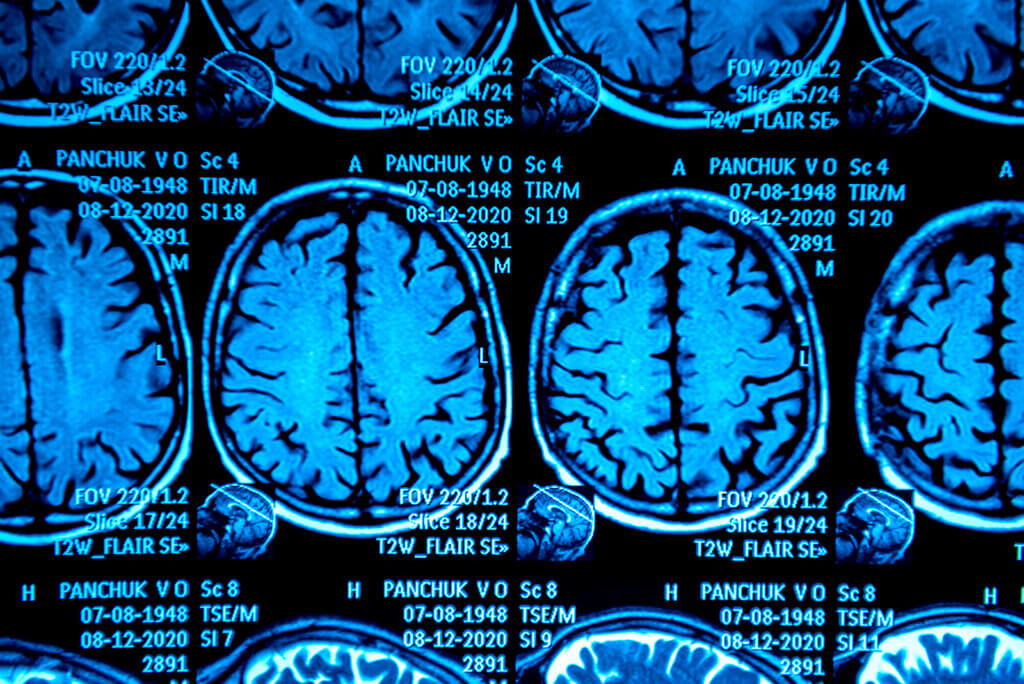

Pruebas de imagen

Algunas de las pruebas de imagen que el médico puede solicitar para confirmar o descartar el diagnóstico de la enfermedad de Parkinson son las siguientes:

- Tomografía computarizada.

- Resonancia magnética nuclear.

- Tomografía de fotón único (SPECT, por sus siglas en inglés).

- Tomografía por emisión de positrones (PET, por sus siglas en inglés).

Las dos primeras pruebas permiten detectar si los síntomas que experimenta la persona son consecuencia de un trastorno estructural o si se trata de párkinson. Los otros dos tipos de tomografía detectan anomalías del cerebro típicas de la enfermedad y de los parkinsonismos.